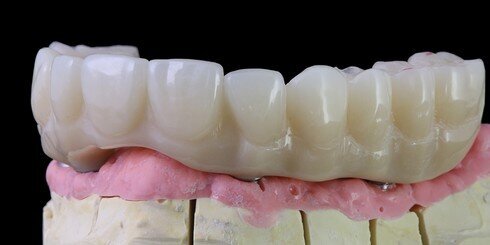

Provizorium TEMPMultilayer

Konstrukce BioHPP a ZolidFX